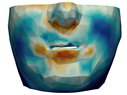

3.3. Simulation Error and Performance

4.1. Analysis of Simulation Accuracy

- Chin. Overall, the amount of error at the chin area is very low. This could be explained by the fact that the skin at the chin is very thin, and the coupling to the mandible makes the simulation highly predictive.

- Lips. In other regions, such as the lips, skin slides strongly over the underlying bones and teeth, and the deformation result is more difficult to predict. Overall, we observe higher variability in the error at the lips, and also some patients with higher error.

- Nose. The quality of the prediction of the deformation of the nose varies strongly across patients. In this case, the variability may depend on the type of surgery performed on each patient’s anterior nasal spine. This type of surgery is not easy to identify in the post-operative CBCT image due to the presence of bone grafts or fixation plates.

- Neck. Finally, we observe large error in the neck area (e.g., patients M5 and M8), and specifically at the junction point between the submental area and the neck (“C point” or “cervical point” in cephalometric analysis). This error was accounted for in our quantitative analysis, which negatively biased the overall results. However, this area is not of special interest to orthognathic surgeons. The deformation is known to be produced by a retraction of skin after surgery, but surgeons do not account for this effect during pre-operative planning.

- Segmentation of the maxilla and mandible. For all patients, the highest error (except for the neck, which is not clinically relevant as discussed above) appears near the cut areas, both of the maxilla (e.g., patients M5 and M7) and the mandible (e.g., patients M1 and M3). This is probably due to the presence of fixation plates and/or bone grafts in the real result (e.g., patient M10, whose maxilla was not segmented, but where the presence of bone graft has been confirmed by the surgeon who carried out the intervention). As a consequence, patients with a segmented maxilla and/or mandible show in general larger error than those without segmented bones. However, the smooth coupling method proposed in Section 2.3.3 reduces considerably the error in cut areas, as shown in Figure 2.

4.3. Comparison of Fine and Coarse Meshes